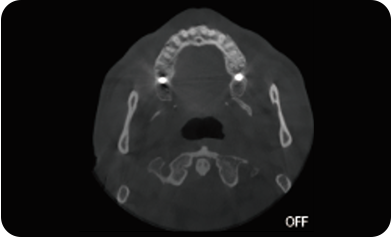

超能去伪 至臻影像

临床样片